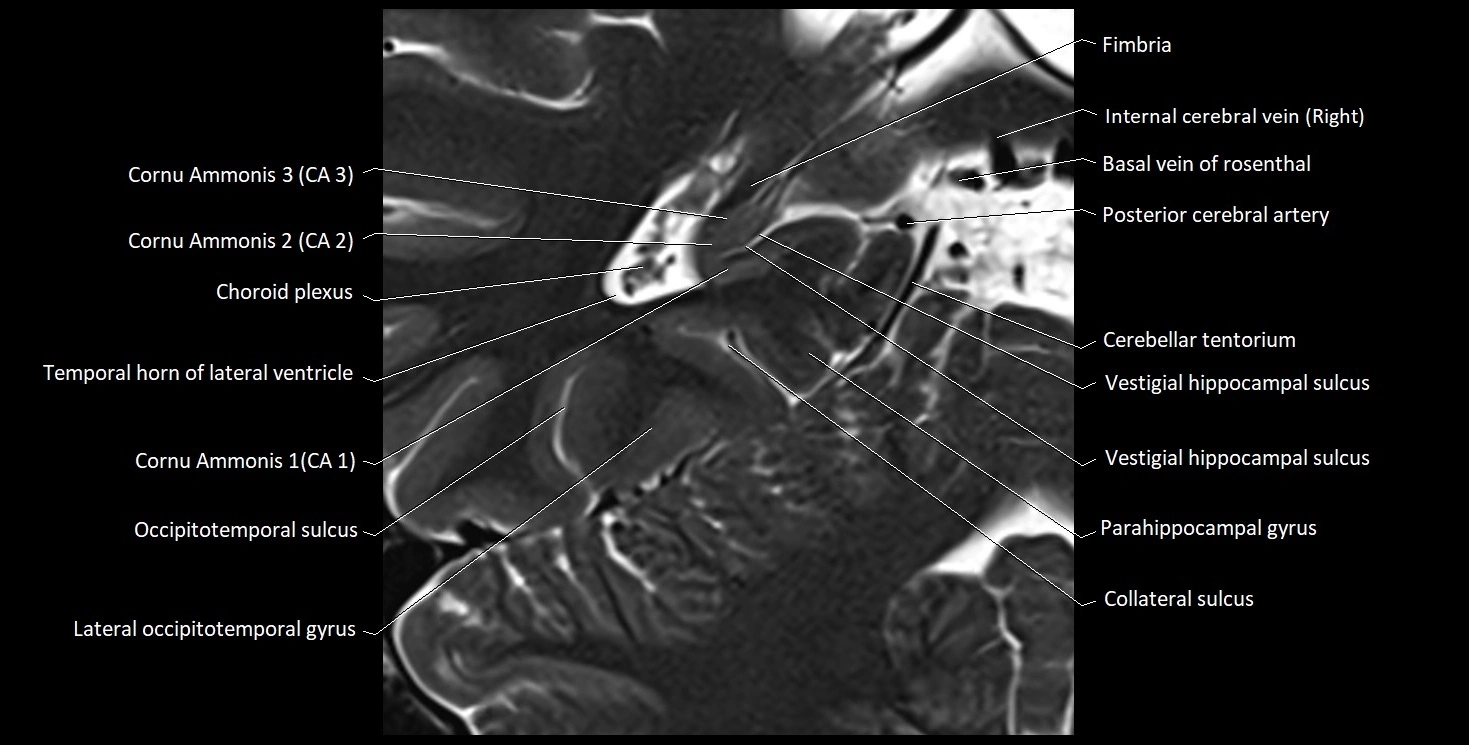

The alveus of the hippocampus is a thin, white matter layer covering the superior (ventricular) surface of the hippocampus within the temporal horn of the lateral ventricle. It consists of myelinated efferent fibers arising primarily from the pyramidal neurons of the hippocampus. These fibers converge medially to form the fimbria of the hippocampus, which continues posteriorly into the fornix, forming a crucial part of the Papez circuit involved in memory consolidation and emotional processing.

The alveus serves as the initial output pathway of the hippocampal formation, linking it to other limbic structures including the hypothalamus, mammillary bodies, and cingulate gyrus. Because of its intimate relationship with the hippocampal head and tail, it is often evaluated in cases of temporal lobe epilepsy, hippocampal sclerosis, and neurodegenerative diseases.

Location and Structure

• Position: Lies on the ventricular (superior) surface of the hippocampus, beneath the ependyma of the inferior horn of the lateral ventricle.

• Composition: A thin sheet of myelinated axons derived mainly from hippocampal pyramidal cells.

• Course: Fibers run medially along the hippocampal surface to form the fimbria of the hippocampus, which curves upward and backward into the fornix.

• Relations:

• Superiorly: Ependyma and CSF of the temporal horn of the lateral ventricle

• Inferiorly: Pyramidal cell layer of the hippocampus (CA1 region)

• Medially: Fimbria and fornix

• Laterally: Temporal lobe white matter and parahippocampal gyrus

MRI Appearance

T1-weighted images:

• Alveus: Thin linear high signal band (due to myelinated fibers) overlying the hippocampal gray matter.

• Hippocampal gray matter: Intermediate signal intensity.

• CSF of lateral ventricle: Dark (low signal).

T2-weighted images:

• Alveus: Low signal line overlying brighter hippocampal gray matter.

• CSF: Bright hyperintense.